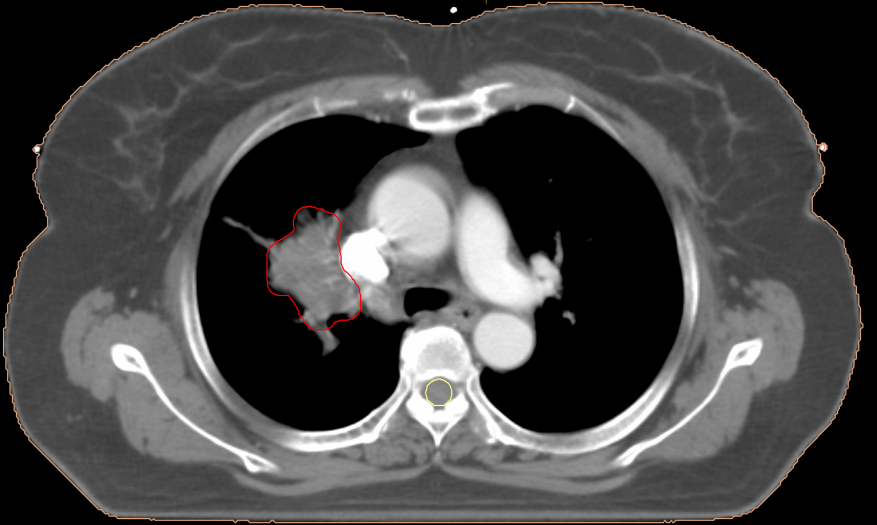

红色圈内代表病灶